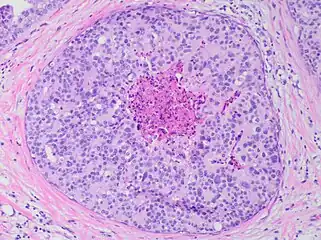

Histopathology of dystrophic microcalcifications in DCIS, H&E stain.

Ductal carcinoma in situ with comedo necrosis spanning 30% of its diameter, which is generally regarded as the minimal size to classify it as comedo.[29]